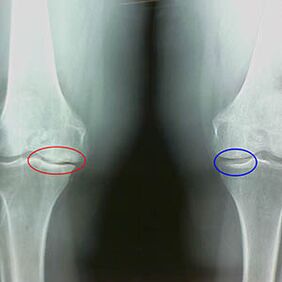

Põlve artroosi teise etapi varased X -RAY tunnused:

- Sääreluudevaheliste tuberkurite teravad servad, kuhu on kinnitatud ristikujuline ligament;

- Liigese lõhe kitsendamine mediaalsel küljel;

- Luude kondüülide teravad servad mediaalsetel külgedel, harvemini külgsuunas - sõltuvalt valguse või vuugiliigese deformatsiooni arengust.

Larseni teise etapi jaoks Liigese lõhe kitsendamine enam kui 50% on iseloomulik, kuid seda saab kontrollida ainult dünaamikas või võrdluses erineva liigesega.